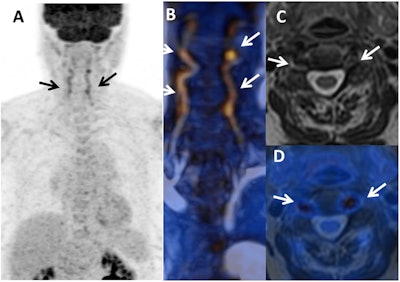

Their study included 13 consecutive patients (median age, 67 years; range, 23-87 years), who underwent a total of 18 PET/MRI scans (10 exams for Takayasu's arteritis and eight scans for giant cell arteritis). PET/MRI scans were performed with a hybrid system (Signa PET/MRI, GE Healthcare) to allow for simultaneous acquisition of PET and 3-tesla MR images. Four scans were performed at diagnosis, seven scans to determine if patients had relapsed, and seven scans conducted during remission.

PET images were interpreted for FDG uptake to signal inflammation, while delayed-enhancement MR images were reviewed to determine any thickening of the aortic wall and luminal narrowing and dilation. The researchers targeted 11 arterial segments: four aortic segments, right and left common carotid arteries, right and left subclavian arteries,vertebral arteries, and common iliac and femoral arteries. Within those segments, they looked for three particular patterns in the PET/MRI results:

- Inflammatory patterns with positive FDG uptake in PET images and abnormal MRI with stenosis and/or wall thickening

- Fibrosis patterns with negative FDG uptake in PET images and abnormal MRI stenosis and/or wall thickening

- Normal patterns with negative results in both modalities

Among the 18 PET/MRI scans, Laurent and colleagues observed an inflammatory pattern in eight results (44%) and a fibrous pattern in three cases (17%). The remaining seven scans (39%) were normal.

When the researchers compared the 10 PET/MRI scans performed on the six TA patients, they discovered an inflammatory pattern in all five patients (100%) with active TA. Only two (20%) of the PET/MRI scans were normal. Among the seven GCA patients who underwent a total of eight PET/MRI scans, inflammation was found in three (50%) of the six patients with active GCA. The hybrid modality also uncovered vascular signs in four (80%) of the five active TA patients and three (50%) of the six GCA patients.